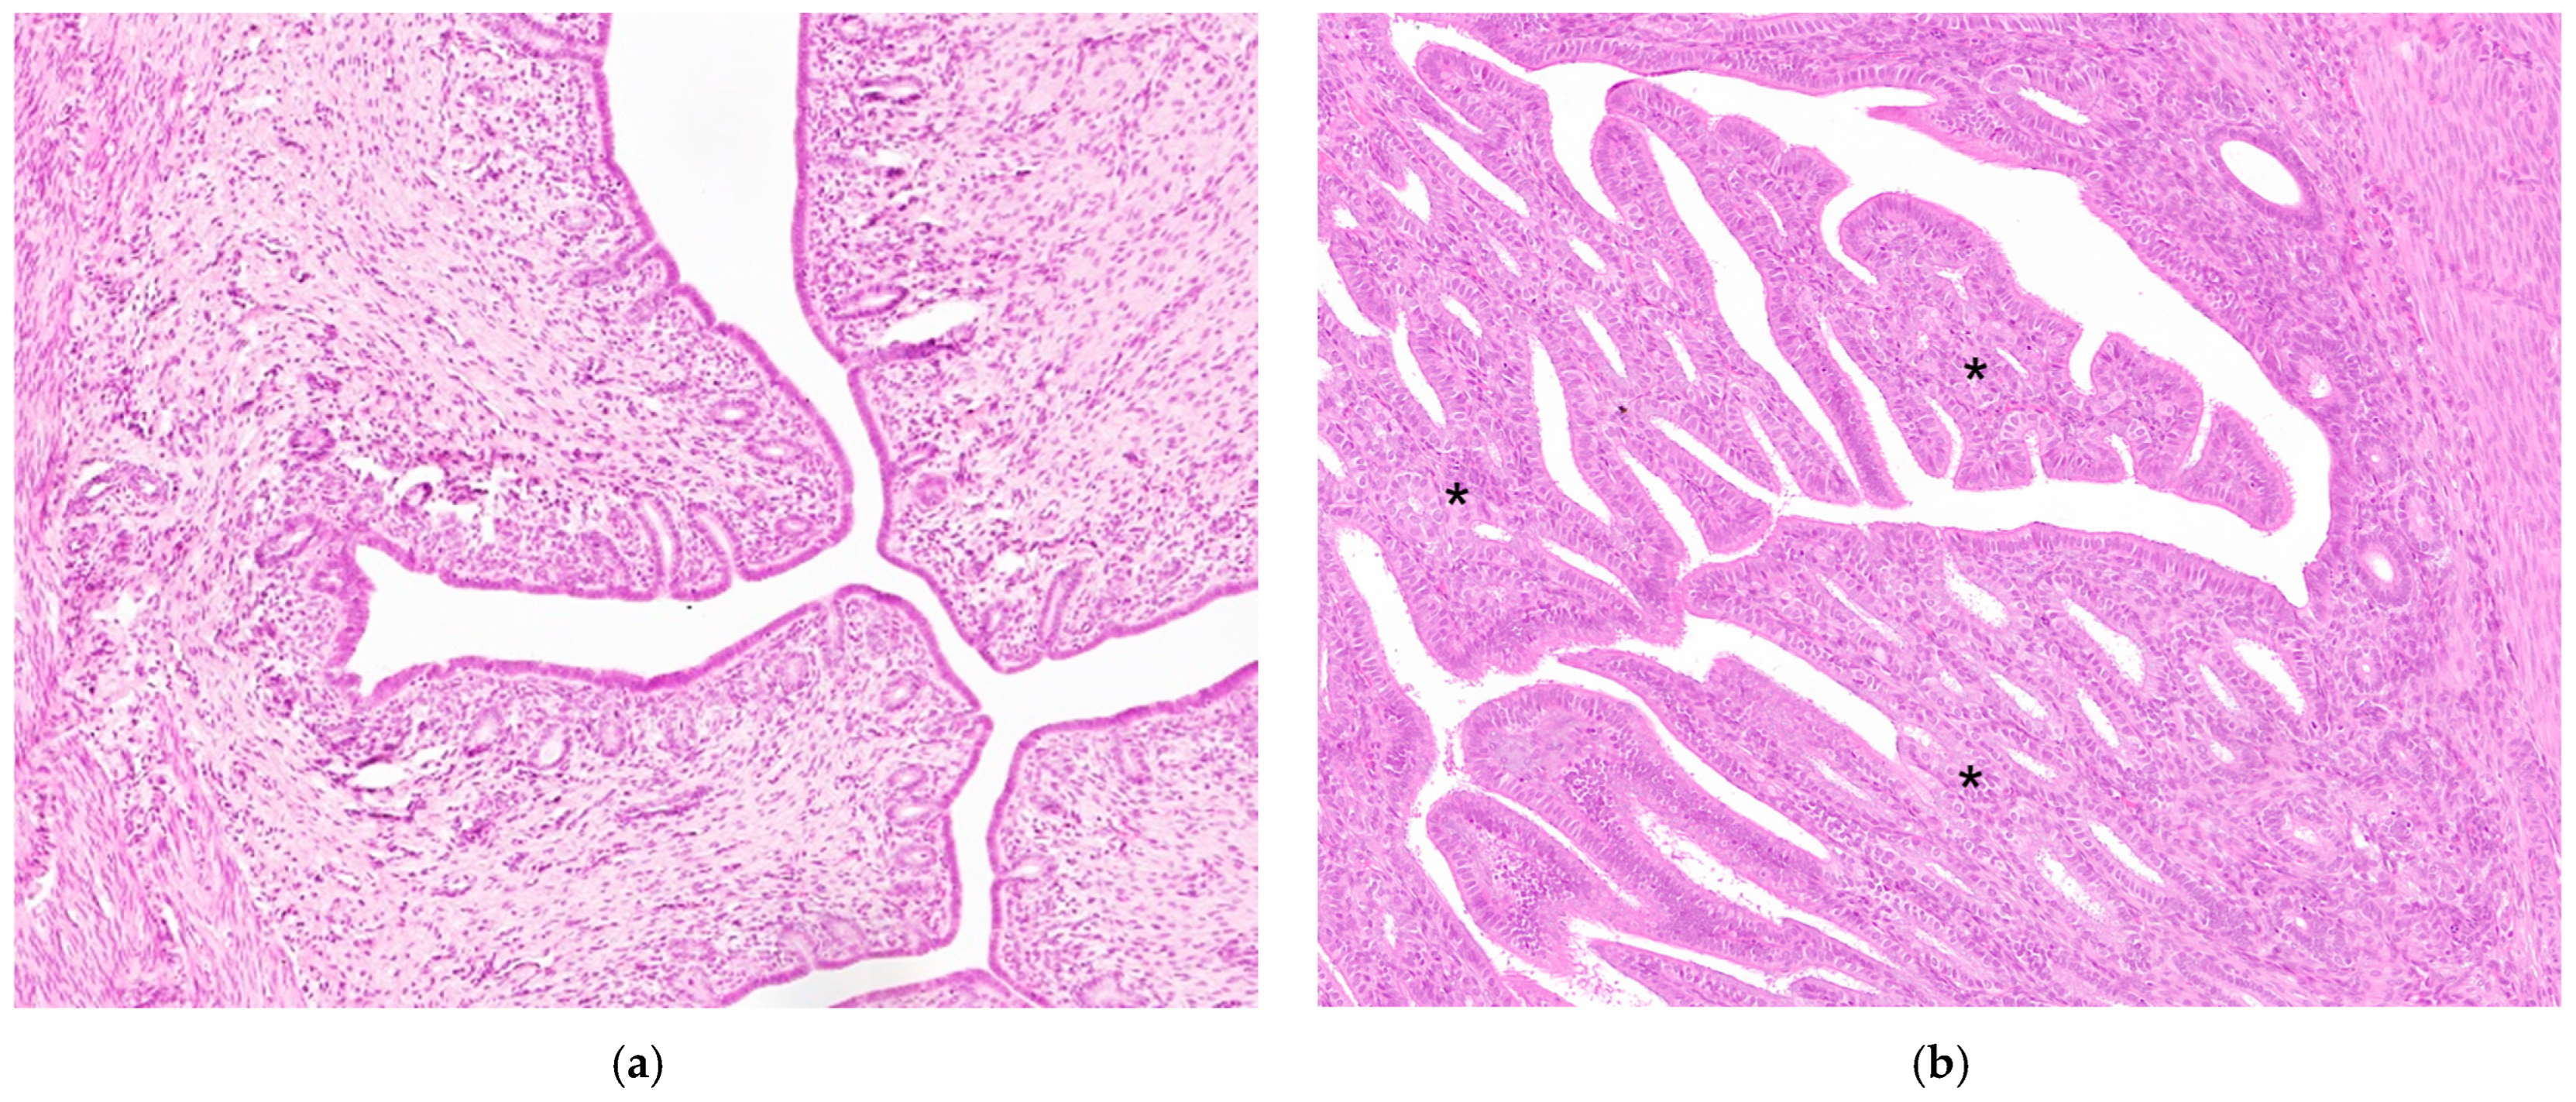

3.2. Histopathological Evaluation

3.3. Immunohistochemistry